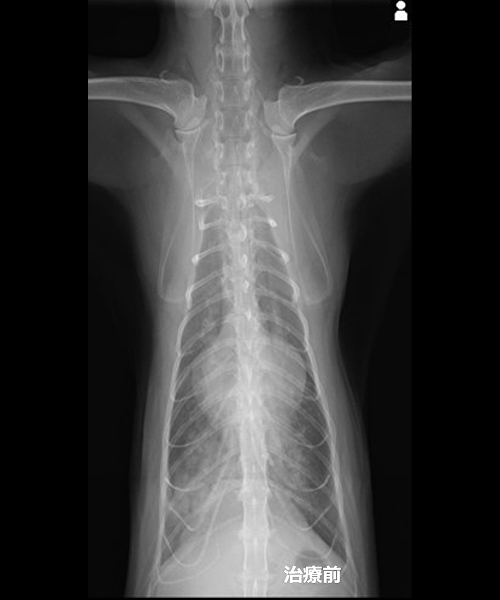

循環器科で僧帽弁閉鎖不全症と診断された犬の胸部X線検査画像

僧帽弁は左心室と左心房の間にある弁で、左心室から大動脈へ血液を送り出す時に血液が左心房へ逆流するのを防いでいます。この弁が変性し上手く閉まらなくなると、血液が左心室から左心房へ逆流します。血液の一部が逆流することにより、全身へ上手く血液を送り出せなくなります。

初期の段階では心臓が頑張って働くことにより、全身には大きな影響はありません。

しかし、頑張り続けた心臓が限界を迎えると血液を十分に送れなくなり、心不全の状態になります。早期の場合、無症状です。定期検診時の身体検査で、心臓に雑音が認められることによって発見されることがほとんどです。

心臓外科手術後の胸部X線検査画像、心陰影が縮小していることがわかる

最初に認められる症状は咳です。これは、逆流した血液によって大きく膨らんでしまった左心房が、その上にある気管支を圧迫することによって生じます。更に病気が進んでくると、疲れやすくなったり痩せてきたりといった症状が出てきます。

心不全の状態へ進行すると肺の中で血液が鬱滞し肺水腫となります。肺水腫になると酸素交換が上手く出来なくなるため酸欠状態となり、呼吸が荒くなったり舌の色が紫色になったります。